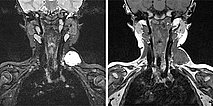

In coronal MRI (left image: T2-weighted, right image: non-enhanced T1-weighted), the venous malformation (VM) is very well delineated. It is strongly hyperintense in the T2 image, whereas it is isointense to the musculature in the non-enhanced T1 image. The signal intensity is typical of the character of a slow-flow lesion.

In coronal MRI (left: T2-weighted, right: T1-weighted non-enhanced) slightly more dorsally, a larger thrombus within the venous malformation is very well delineated. In the T2 image, this is hypointense compared to the severely hyperintense venous malformation. In the non-enhanced T1 image it is slightly more hyperintense than the surrounding hypointense venous malformation.